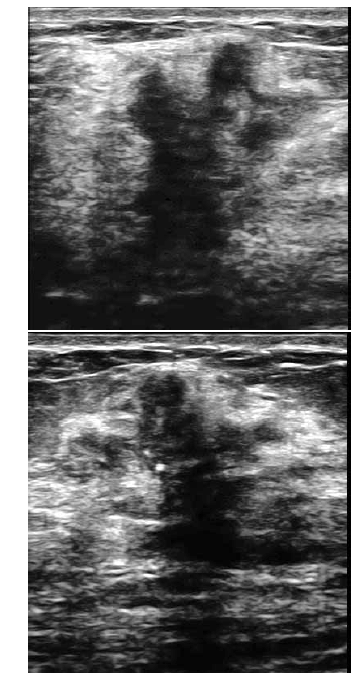

Uma paciente de 32 anos de idade procurou um médico ginecologista por ter palpado nódulo na mama direita. Ao exame das mamas, foi percebido nódulo endurecido, fixo aos planos adjacentes, com cerca de 3 cm de diâmetro. Foi realizada, então, mamografia, que revelou presença de lesão espiculada, com limites imprecisos, retração do parênquima adjacente e microcalcificações pleomórficas agrupadas. O exame ultrassonográfico evidenciou a lesão representada na forma gráfica na figura abaixo.

A respeito dessa situação hipotética, julgue os itens de 75 a 80.

O estudo histopatológico está sempre indicado para a categoria IV, segundo proposta do BI-RADS ultrassonográfico.

Segundo a classificação do BI-RADS ultrassonográfico, essa imagem poderia ser enquadrada na categoria IV-b.